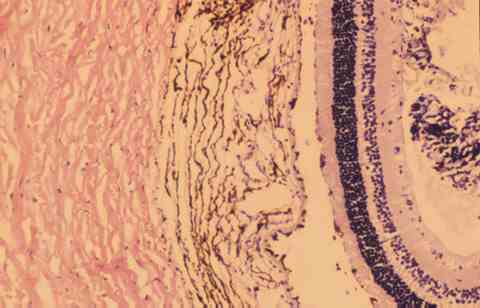

Figura 5

CORTE HISTOLÓGICO EN PARAFINA HE, MISMA ZONA DE LA FIG. 4. SE OBSERVA UNA ARQUITECTURA DE LA RETINA NORMAL EN EL ÁREA EN CONTACTO CON LAS CÉLULAS TRASPLANTADAS.